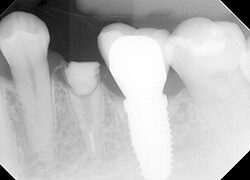

【治療前】

左下5番(第2小臼歯)がコアごと脱離してきて、カリエスを除去したところ、ほぼ骨のレベルに至る残根となりました。

6番(第1大臼歯)にインプラントが入っているのもあり、ご本人はインプラントにして欲しいとのことでしたが、歯根長も十分にあるので矯正的挺出をご提案しました。